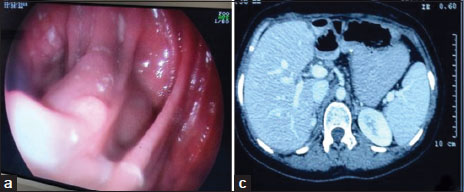

She had similar complaint 1½ years back, for which she was investigated and treated as a case of gastric lymphoma at a private hospital. Investigations done included contrast-enhanced computerized tomography of the abdomen showing marked diffuse circumferential mural thickness seen involving distal body of the stomach and antropyloric region with luminal compromise, suggestive of mitotic etiology [Figure 1]a.

| Figure 1 Computed tomography showing growth in the stomach, (b) endoscopic view of growth in distal stomach

Her upper gastrointestinal tract (UGI) endoscopy [Figure 1]b with antral biopsy showed poorly differentiated neoplasm suggestive of lymphoma. Immunohistochemistry was diagnostic of large B-cell lymphoma with markers positive (CD20, CD43, CD79, Ki67, and LLA positive). Bone marrow biopsy did not show involvement by lymphoma.